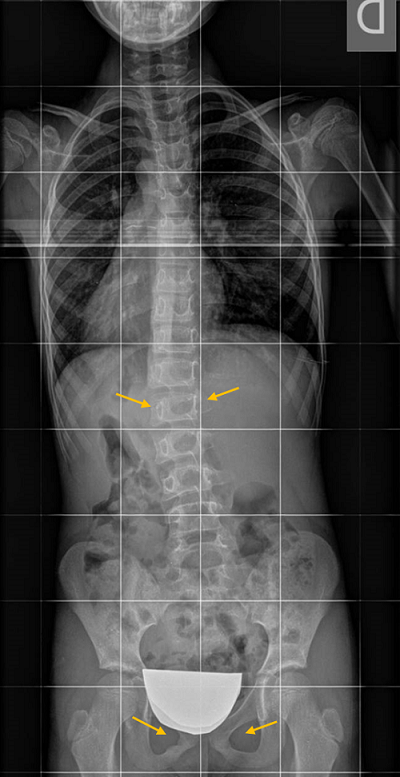

En cuanto a las imágenes de vértebras rotadas, si el paciente gira el tronco, o si la placa no incide perpendicular al plano coronal del paciente, aun manteniendo la pelvis centrada, pueden verse giradas, con un falso índice de Moe (se explica más adelante). Por eso es muy importante visualizar los puntos que permiten valorar la simetría de una proyección correcta (Figura 7).

Figura 7. La L2 está muy rotada, como correspondería a una curva más grave, pero comprobamos que radiografía no está perfectamente simétrica, porque en la zona isquiopubiana los agujeros obturadores no se ven simétricos. Todo el tronco está rotado. A veces es difícil analizar estos agujeros porque se tapan con el plomo protector de los ovarios, o porque se colima tanto que se cortan la pelvis y los agujeros. Mostrar/ocultar